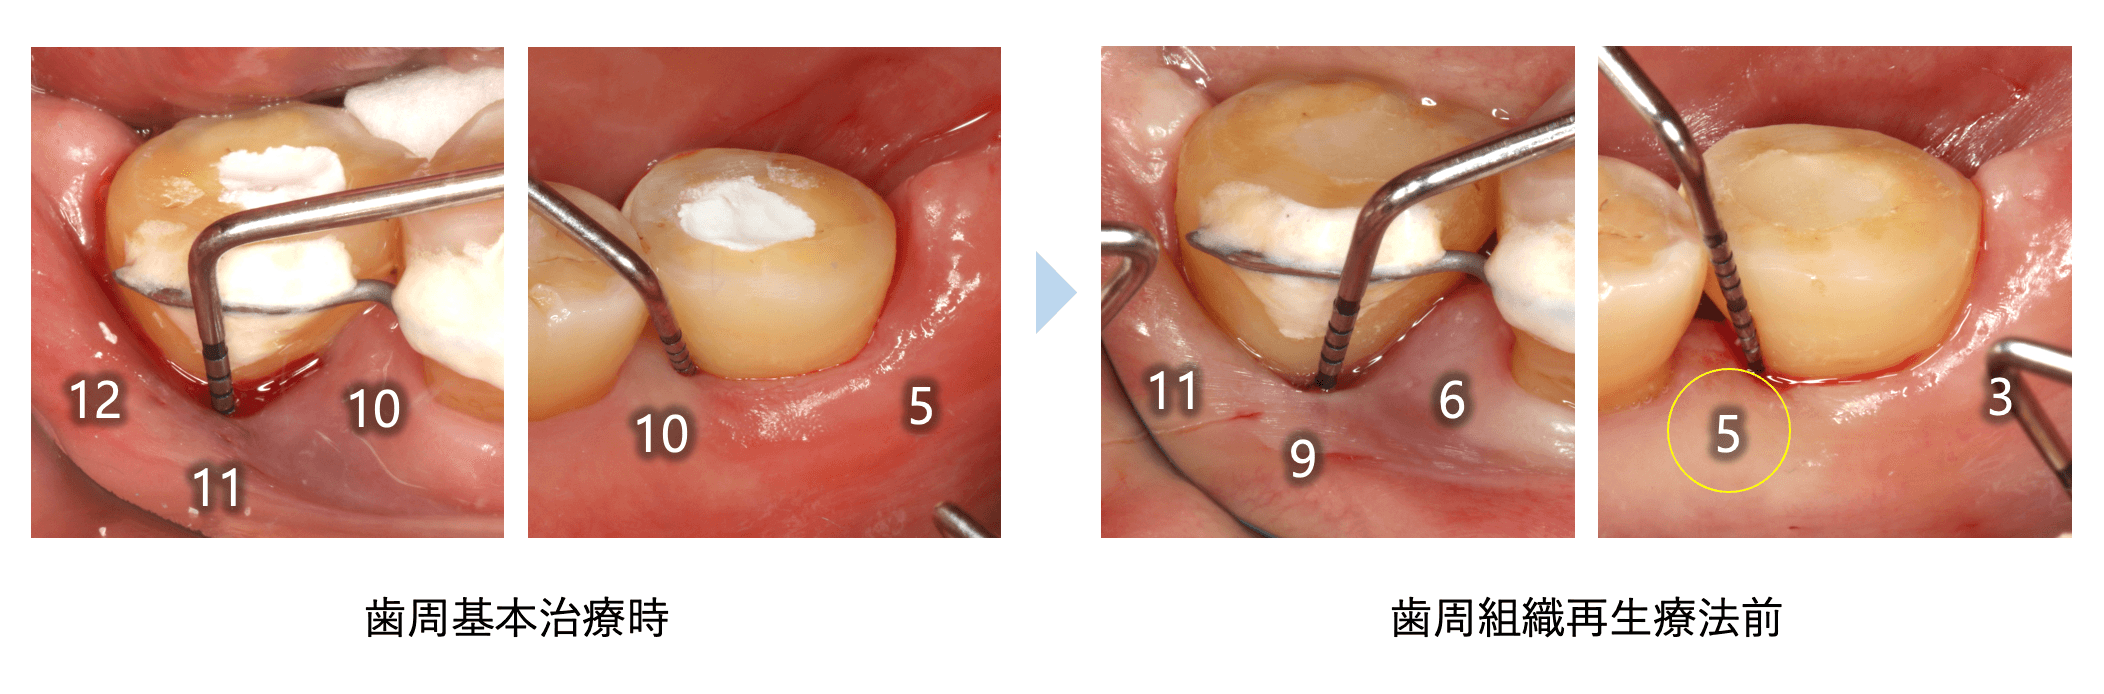

歯周基本治療時と再生療法前のプロービング検査の結果です。頬側は全体的に浅くなり近心舌側は10mmから5mmに改善しました。

- 術前:動揺度3度、PDは遠心から11mm、9mm、6mmと深い状態

- 術後1年5ヶ月:PD=5mmに改善 動揺度も0〜1度に改善